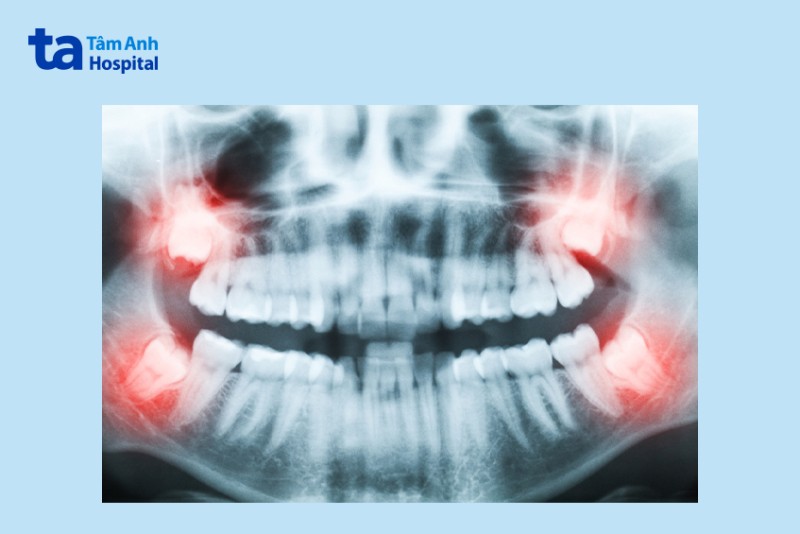

Khi răng khôn mọc sai vị trí như mọc mắc vào nướu, mọc dưới nướu, mọc lệch,… thì người bệnh sẽ được chỉ định nhổ răng khôn bởi khi răng khôn mọc sai vị trí sẽ ảnh hưởng đến tình trạng sức khỏe, gây viêm nhiễm, nhiễm trùng.

Dấu hiệu nhận biết răng khôn mọc lệch sai vị trí là người bệnh cảm thấy đau nhức, sưng tấy, khó chịu, khó cử động hàm,…